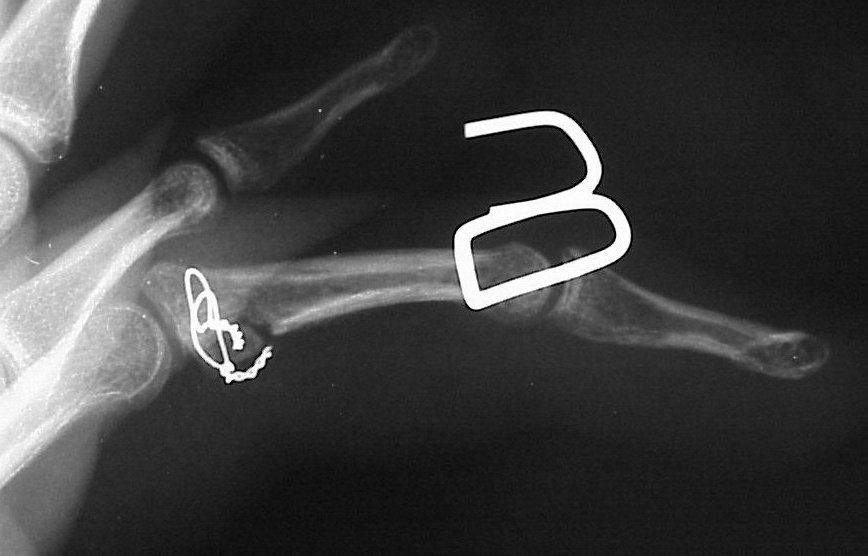

First impression was that the palmar fragment was probably big enough to take down and reinsert. However, comparison of films shortly after the fracture (above) and at two months (below) confirms the injury as a healed comminuted central impaction fracture with splay and hinging of the volar cortex.